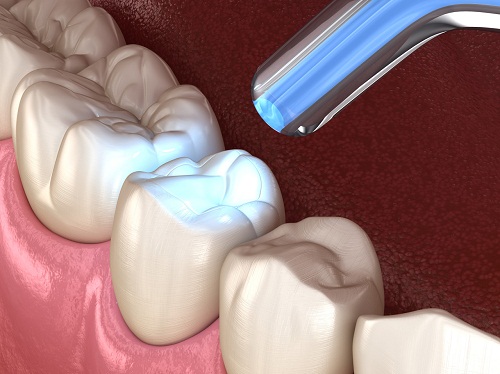

浅龋齿的治疗相对简单直接。在早期阶段,可以通过专业洁治、局部涂氟或使用渗透树脂等技术促进釉质再矿化,恢复牙齿的矿物质含量。如果龋坏范围稍大,牙医可能会建议进行预防性树脂充填,这是一种微创的治疗方法,仅去除少量龋坏组织后即进行充填。

深龋齿的治疗则更为复杂,需要根据牙髓状态制定个体化方案。治疗需要先完全去除龋坏组织。如果去龋后发现牙髓尚未受到感染,牙医可能会在洞底放置保护性材料进行安抚治疗,观察一段时间后再进行长久性充填。如果龋坏已经导致牙髓感染,则需要进行根管治疗,完全清除感染的牙髓组织,完善根管预备、消毒和充填后,再进行牙体修复。